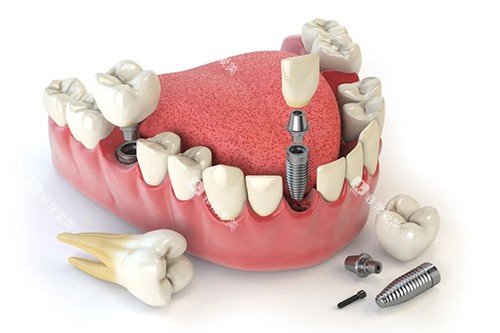

上海美田口腔门诊部的诊疗科目涵盖种植修复、牙齿矫正、牙周治疗等 11 个科室,能够满足不同患者的口腔诊疗需求。

无论是牙齿缺失需要种植修复,还是牙齿不整齐需要矫正,亦或是牙周疾病需要治疗,患者都能在这里找到特色的解决方案。